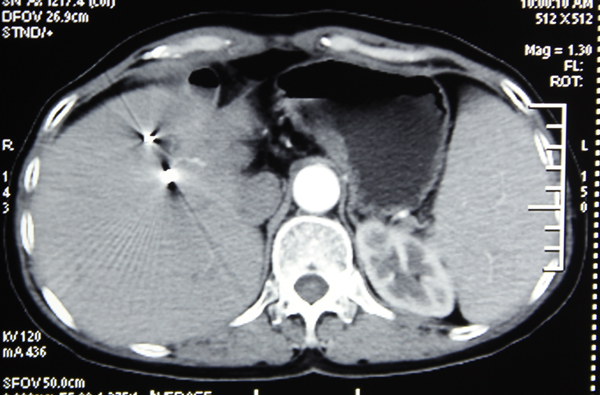

2003年的一天,携带乙肝病毒20余年的李阿姨由于上腹部不适10余天而入住我院肝病内科。入院检查发现肝功能A级,肝脏CT显示肝前叶巨块型肝癌,肿瘤大小为6.0×6.8×6.0cm,包膜完整,但未见癌栓形成。若不采取积极治疗,李阿姨的生存期约只有6个月左右,且随着病情的发展,生存期将会倒计时……。

李阿姨在我院经过“三联疗法”治疗后,再结合长期使用中草药辨证治疗,较好地控制了肝癌的发展。经多次复查肝CT、磁共振等提示肝内病灶稳定并逐渐缩小2-3厘米。至今,她带瘤生存了12年,目前李阿姨像正常人一样生活。

肝癌李秀英2012.6CT右叶肿瘤2厘米,下两个分别为0.5厘米